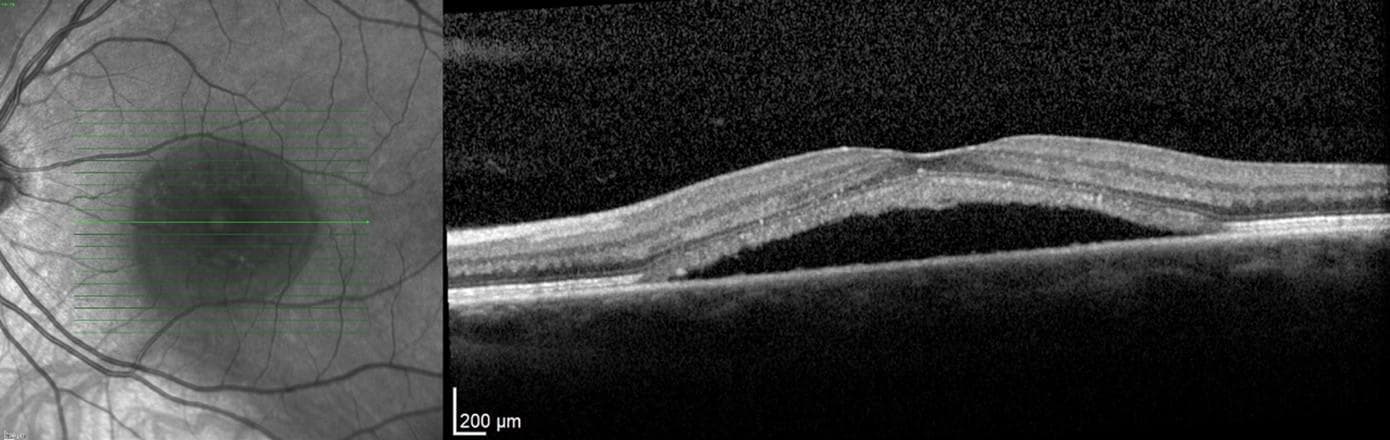

Central Serous Chorioretinopathy: Evolving Understanding, Investigations, and Treatment Options

Central serous chorioretinopathy (CSCR) is an idiopathic retinal disease in which fluid accumulates below the neurosensory retina, causing a serous detachment. CSCR has been typically viewed to be benign due to its self-limiting nature. However, as some cases can be chronic, management can be challenging. Over recent years there have been major evolutions in how we view and manage this classic disease, through deeper pathophysiological understandings and the availability of new treatment options and imaging tools.